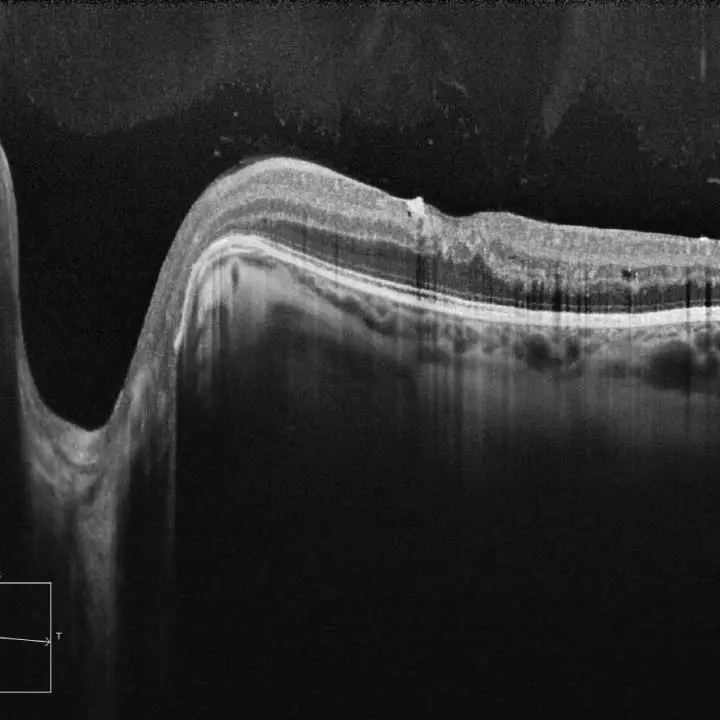

Optical Coherence Tomography (OCT) is a non-invasive imaging technology used to capture detailed cross-sectional images of the retina, the light-sensitive tissue at the back of the eye. Similar to an ultrasound, which uses sound waves to create images of internal organs, OCT uses light waves to produce high-resolution images of the retina and optic nerve. This advanced diagnostic tool allows our optometrists in Edmonton to observe the different layers of the retina, providing essential insights into the health of your eyes.

While both OCT and retinal/fundus photography are valuable diagnostic tools, they serve different purposes. Retinal photography, or fundus photography, captures surface images of the retina, providing a broad view of its condition. In contrast, OCT offers detailed cross-sectional images of the retina's layers, revealing more intricate, below the surface, details that are not visible with standard retinal photography. OCT is particularly useful for detecting and monitoring conditions that affect the deeper structures of the retina and optic nerve.